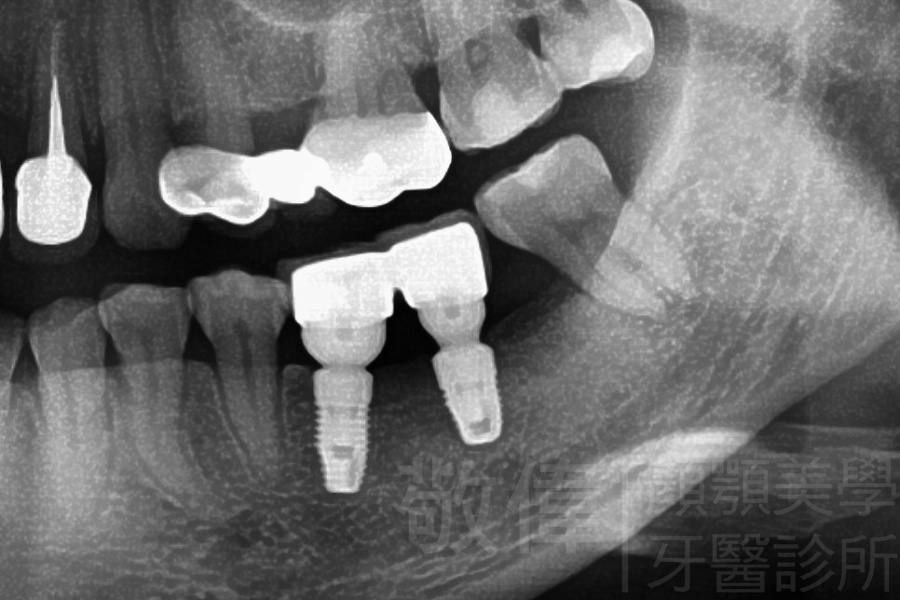

人工植牙/左下第1、2大臼齒植牙

治療前-下顎全口   治療後-下顎全口

治療前-缺牙區X光   治療後-大臼齒X光